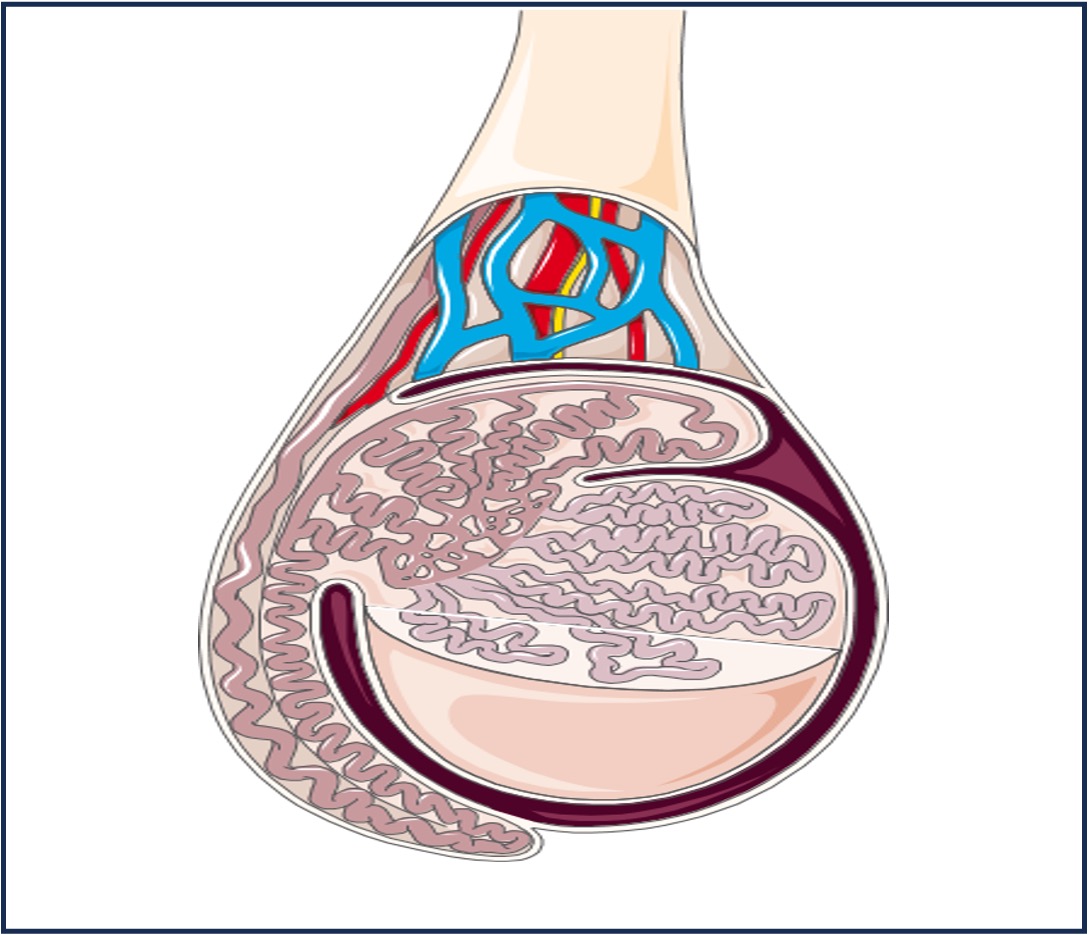

Males:

FSH acts on the testes to trigger the activation of spermatogenesis, while LH is responsible for the production of testosterone

Testosterone is the sex hormone (steroid) that promotes the development of the secondary sex characteristics in males

These secondary sex characteristics include the development of body hair, increased muscle mass and deepening voice

Testosterone